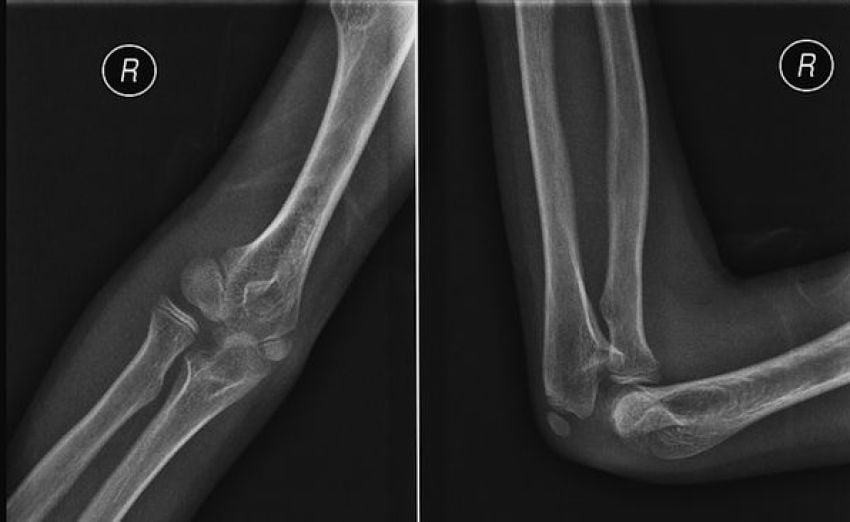

Основной метод диагностики — рентгенография локтевого сустава. При необходимости производится компьютерная томография.

| Степень | Рентгенологическая картина | Эффективность лечения |

| Первая | Появляются небольшие разрастания костной ткани (остеофиты), небольшое сужение суставной щели. Начало перерождения хрящевой основы сустава в костную | Хорошо поддается медикаментозному лечению, ЛФК, физиотерапии. Иногда эффект наступает при соблюдении диеты, двигательного режима, отказа от вредных привычек |

| Вторая | Краевые костные разрастания хорошо видны на снимке, выражено сужение суставной щели | Основное внимание придается медикаментозному (противовоспалительному и противоболевому) лечению, однако предыдущие мероприятия также учитываются |

| Третья | Значительная деформация сустава, полное или почти полное исчезновение суставной щели. Значительные костные разрастания. Внутрисуставные связки утолщены, количество синовиальной жидкости резко снижено | Плохо лечится консервативными методами. Применяется в основном симптоматическое лечение по устранению болевого синдрома. Эффективны хирургические методы |